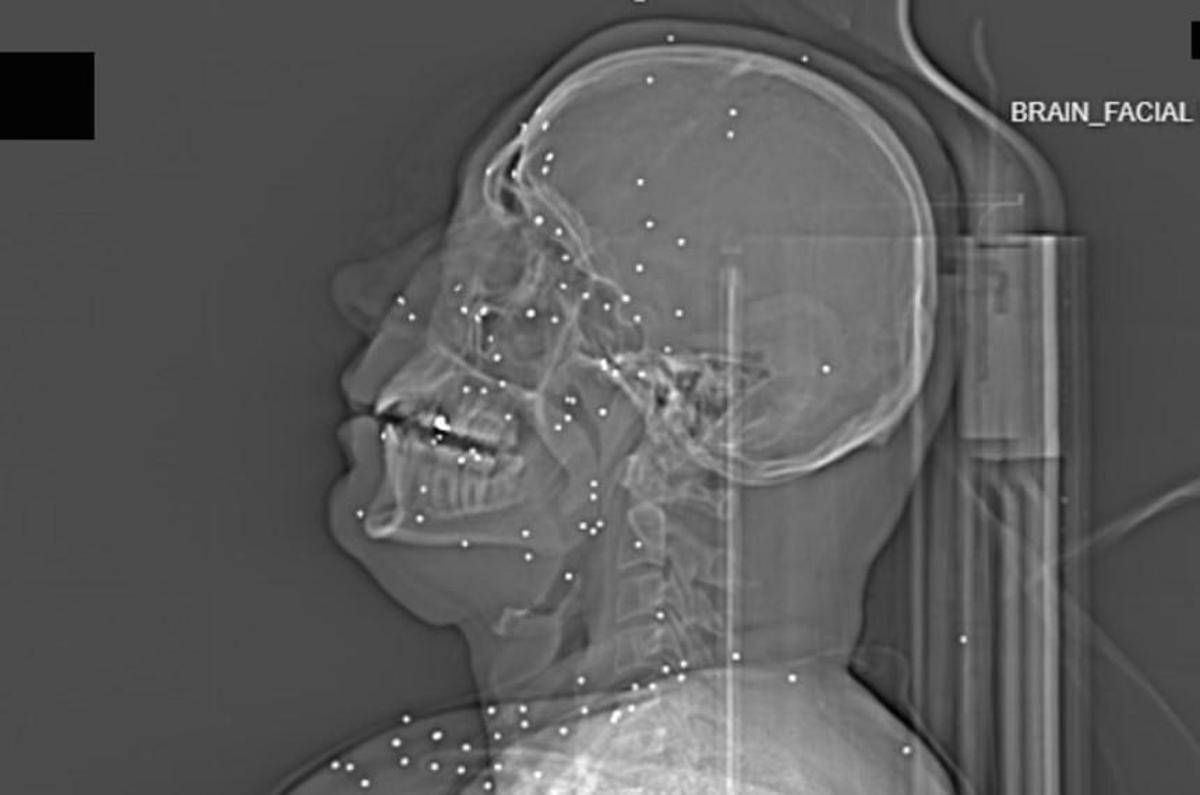

Il volto di Anahita – nome di fantasia, poco più che ventenne – appare come un cielo notturno attraversato da punti luminosi. Piccole sfere metalliche, da 2 a 5 millimetri, disseminate sul viso, nelle orbite oculari, persino nella massa scura del cervello. Sono proiettili “birdshot”, pallini da caccia sparati da un fucile a pompa. A distanza ravvicinata, spiegano gli esperti, non sono affatto “meno letali”: possono frantumare ossa, devastare tessuti molli, perforare facilmente un bulbo oculare. Anahita ha perso almeno un occhio, forse entrambi.

Quell’immagine non è un caso isolato. Fa parte di oltre 75 set di esami diagnostici provenienti da un singolo ospedale di una grande città iraniana, raccolti nel corso di una sola serata, durante la stretta repressiva di gennaio. Una concentrazione temporale che, già di per sé, racconta una dinamica da “mass casualty”, evento con numerose vittime simultanee, tipico degli scenari di guerra o dei grandi disastri.

Le valutazioni, condotte congiuntamente dal Guardian e dalla piattaforma di fact-checking Factnameh, sono state affidate a un panel indipendente di specialisti internazionali: medici d’urgenza, radiologi, esperti di trauma imaging e balistica. Un ex medico iraniano di pronto soccorso, anch’egli consultato, ha confermato la coerenza del software utilizzato per gli esami e l’assenza di segni di manomissione. Gli esperti precisano che, senza cartelle cliniche complete, non è possibile formulare diagnosi definitive sui singoli pazienti. Ma il quadro complessivo, spiegano, è inequivocabile.